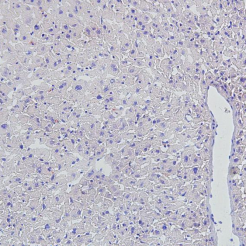

| 脑组织-尼氏染色-冰冻切片 | 脑组织-尼氏染色-石蜡切片 |

| 肝组织-Masson染色-冰冻切片 | 肝组织-Masson染色-石蜡切片 |